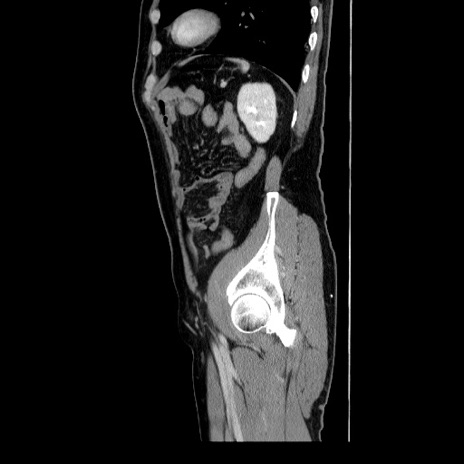

症例34(矢状断像)

【症例】60歳代 男性

【主訴】右鼠径部膨隆

【現病歴】1年程前より右鼠径部膨隆あり。自己にて還納可能だったため放置していた。3時間前より右鼠径部の脱出を認め、還納困難となり受診。

【身体所見】右鼠径部に小児頭大の膨隆あり。弾性硬であり、用手還納は困難。左鼠径部にも膨隆を認める。脱出はなし。